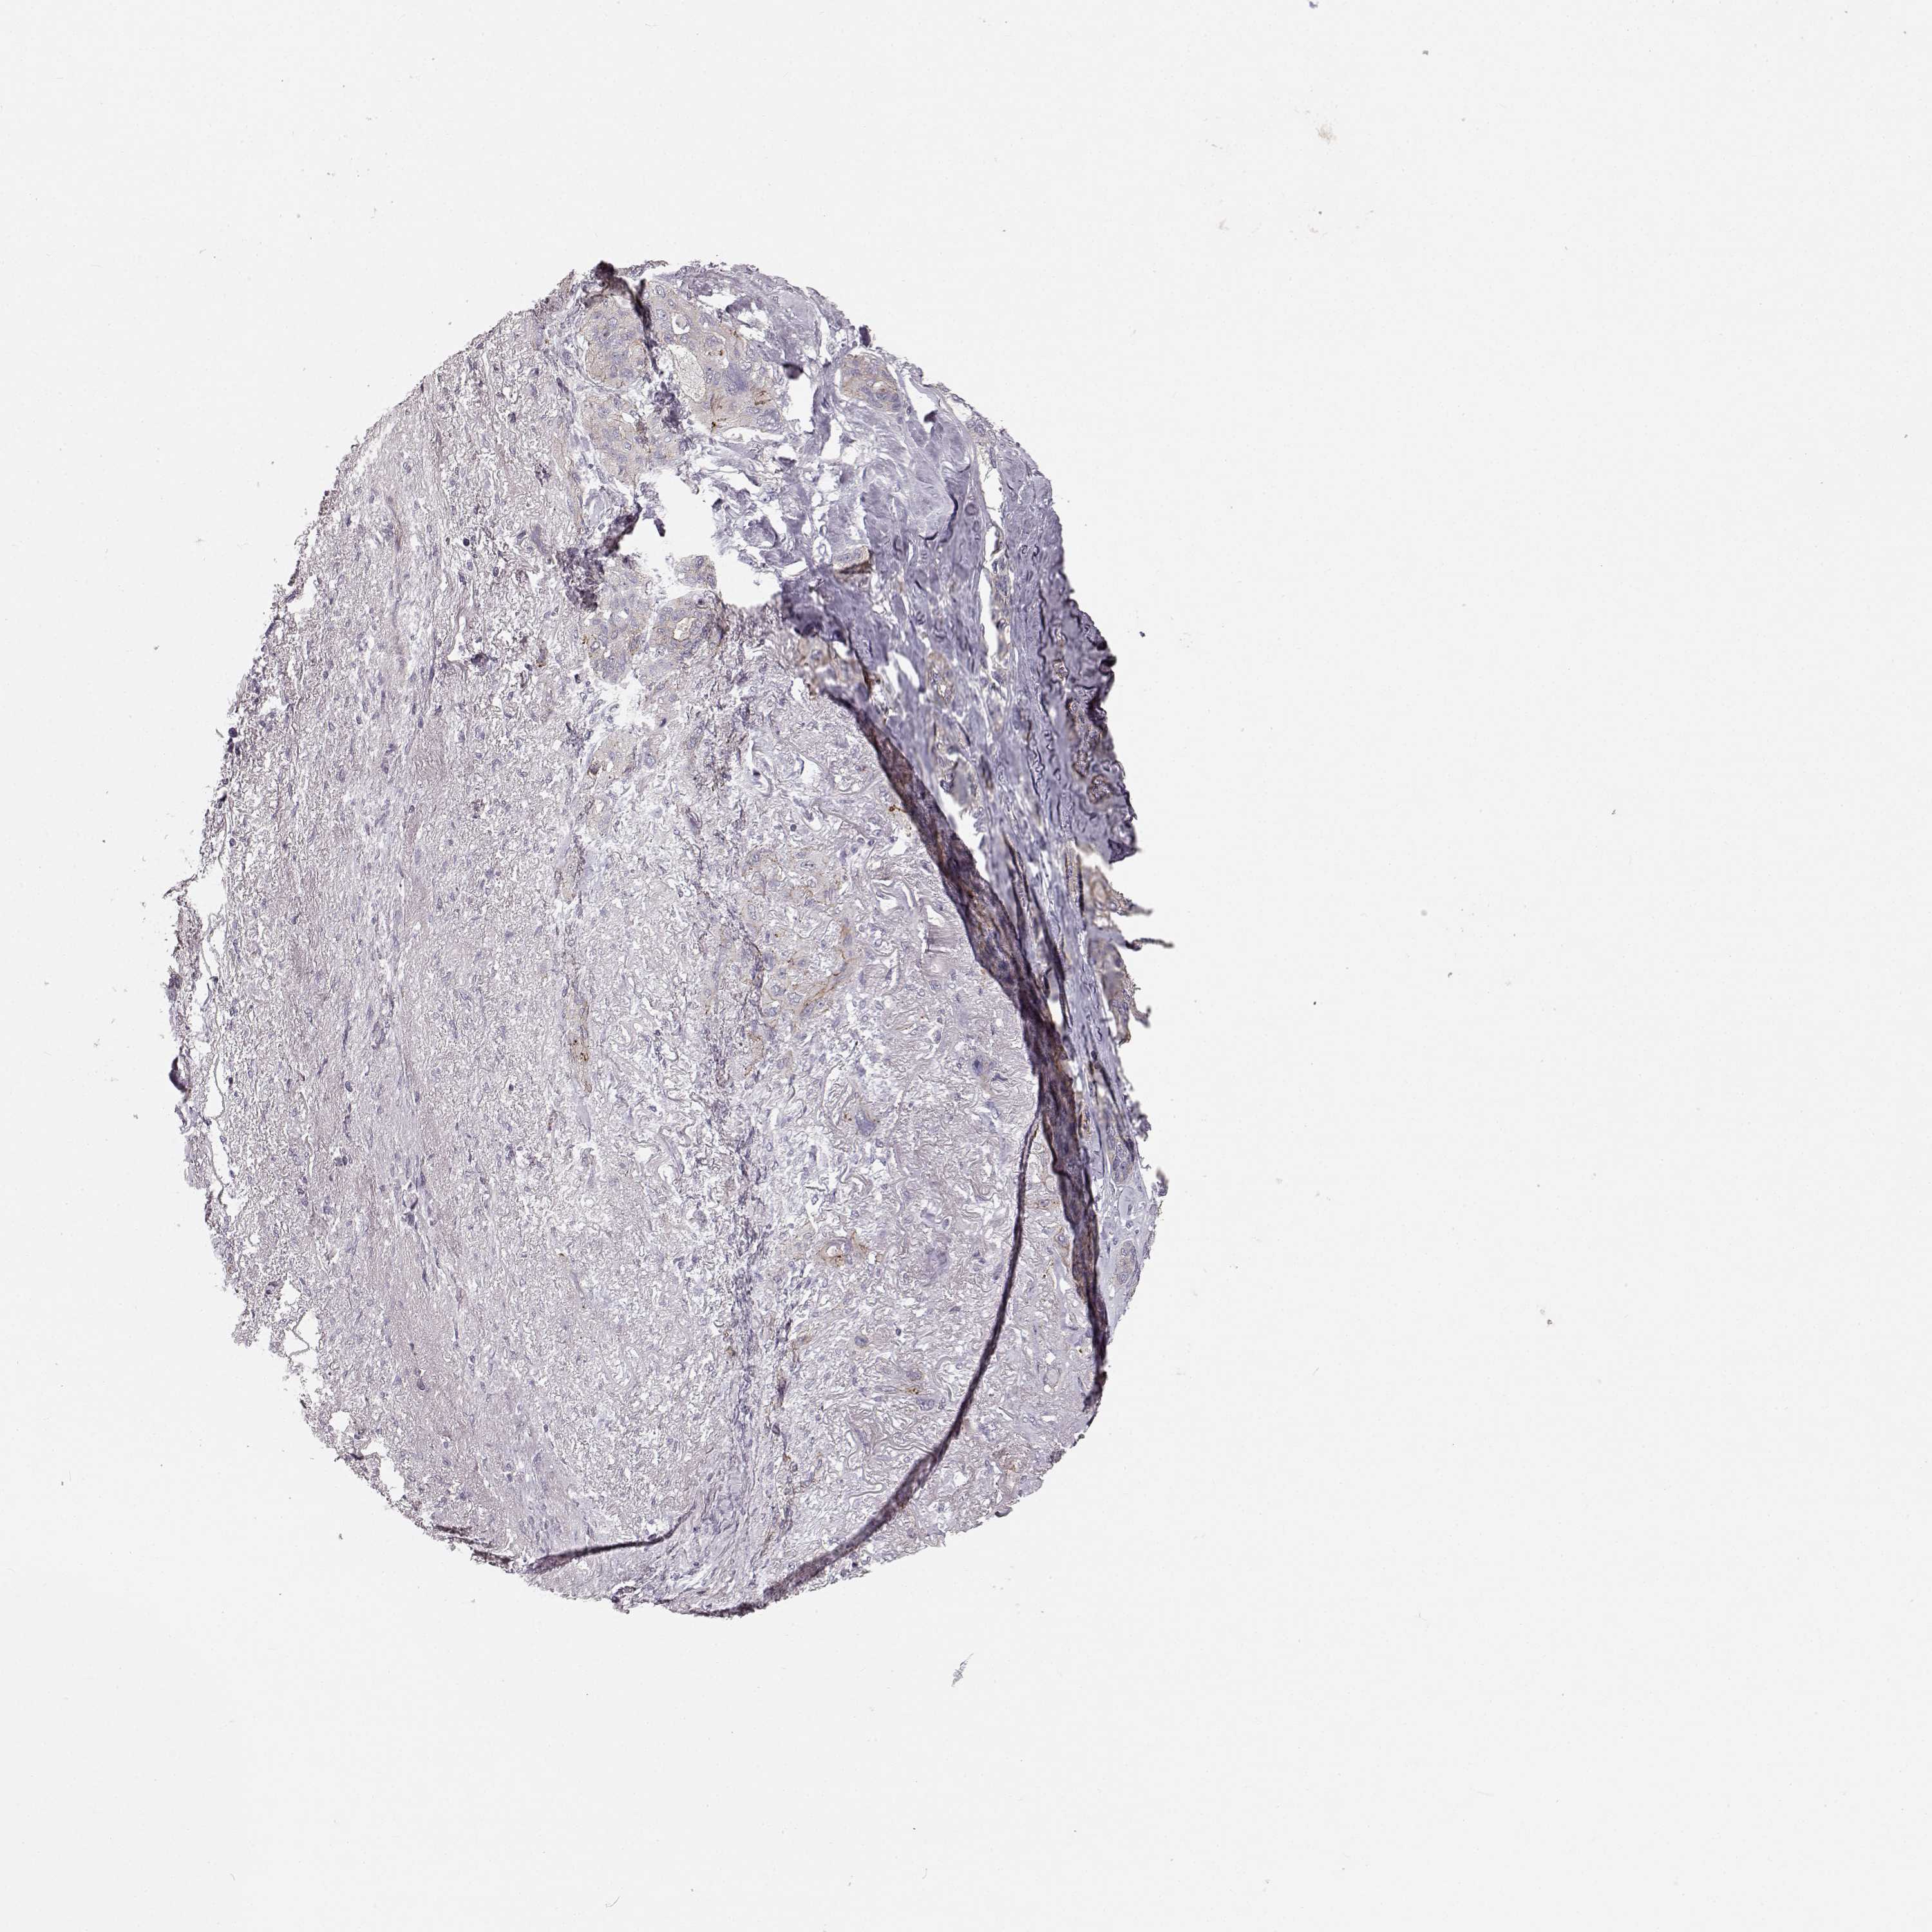

LUNG ADENOCARCINOMA (VALIDATION) - Interactive survival scatter ploti

The Survival Scatter plot shows the clinical status (i.e. dead or alive) for all individuals in the patient cohort, based on the same data that underlies the corresponding Kaplan-Meier plots. Patients that are alive at last time for follow-up are shown in blue and patients who have died during the study are shown in red.

The x-axis shows the expression levels (FPKM) of the investigated gene in the tumor tissue at the time of diagnosis. The y-axis shows the follow-up time after diagnosis (years). Both axes are complimented with kernel density curves demonstrating the data density over the axes. The top density plot shows the expression levels (FPKM) distribution among dead (red) and alive patients (blue). The right density plot shows the data density of the survived years of dead patients with high and low expression levels respectively, stratified using the cutoff indicated by the vertical dashed line through the Survival Scatter plot. This cutoff is automatically defined based on the FPKM cutoff that minimizes the p-score. The cutoff can be changed by dragging the vertical line or by entering a cutoff value in the square labeled "Current cut-off".

Under the Survival Scatter plot the p-score landscape (black curve; left axis) is shown together with dead median separation (red curve; right axis). Dead median separation is the difference in median mRNA expression between patients who have died with high and low expression, respectively. It is calculated as follows: median FPKM expression of dead patients with high expression - median FPKM expression of dead patients with low expression. This is intended to aid the user in visually exploring custom cutoffs and the associated p-scores and dead median separation.

Individual patient data is displayed and can be filtered by clicking on one or more of the category buttons on the top of the page. Categories describing expression level and patient information include: high, low, alive, dead, female, male and tumor stages. The scale of the x-axis can be toggled between linear and log-scale by clicking on the "x log" button. Mouse-over function shows TCGA ID, patient information and mRNA expression (FPKM) for each patient.

& Survival analysisi

Kaplan-Meier plots summarize results from analysis of correlation between mRNA expression level and patient survival. Patients were divided based on level of expression into one of the two groups "low" (under cut off) or "high" (over cut off). X-axis shows time for survival (years) and y-axis shows the probability of survival, where 1.0 corresponds to 100 percent.

SLC22A18 is not prognostic in Lung Adenocarcinoma (validation)

: 3.92

Average pTPM 2.7

Number of samples 105